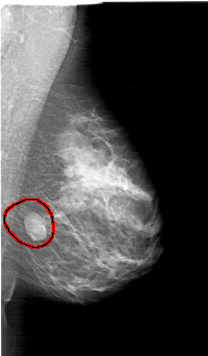

FILE: A_1394_1.RIGHT_CC.OVERLAY

TOTAL_ABNORMALITIES 1

ABNORMALITY 1

LESION_TYPE MASS SHAPE LOBULATED MARGINS CIRCUMSCRIBED

ASSESSMENT 4

SUBTLETY 5

PATHOLOGY BENIGN

TOTAL_OUTLINES 1

BOUNDARY